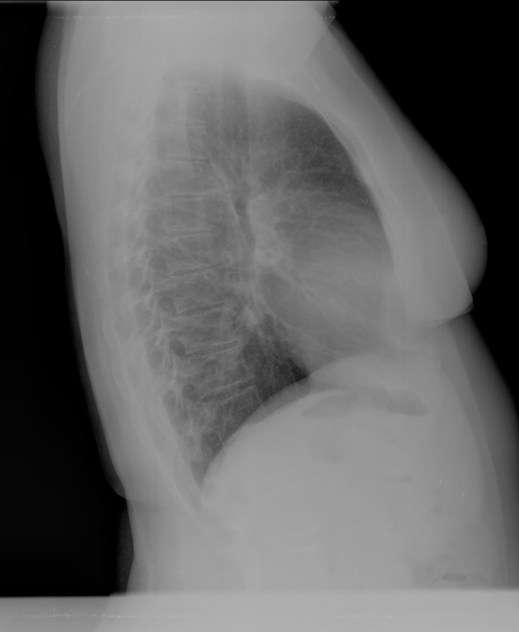

CASO: Febrícula y tos de 4 días de evolución.

Hallazgos:

- En la placa PA se observa una asimetría en los hilios pulmonares, el hilio izquierdo tiene una densidad aumentada.

- Tras examinar la placa lateral se observa un aumento de densidad en la columna que puede ser compatible con una condensación, es el signo de la desnificación vertebral.

SIGNO DE LA DENSIFICACIÓN VERTEBRAL: En la radiografía lateral normal, la densidad de la columna torácica tiende a disminuir desde la parte superior hasta el diafragma; la alteración de ese patrón por la presencia de una densidad superpuesta a la columna, indica la existencia de una consolidación pulmonar. Este signo adquiere especial valor cuando en la proyección posteroanterior la consolidación está oculta en el espacio retrocardíaco o en la base pulmonar.